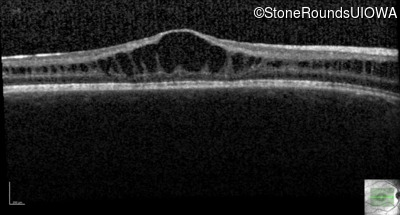

Optical Coherence Tomography - Left - 20/50

Exemplar / OCT Stack

OCT Stack